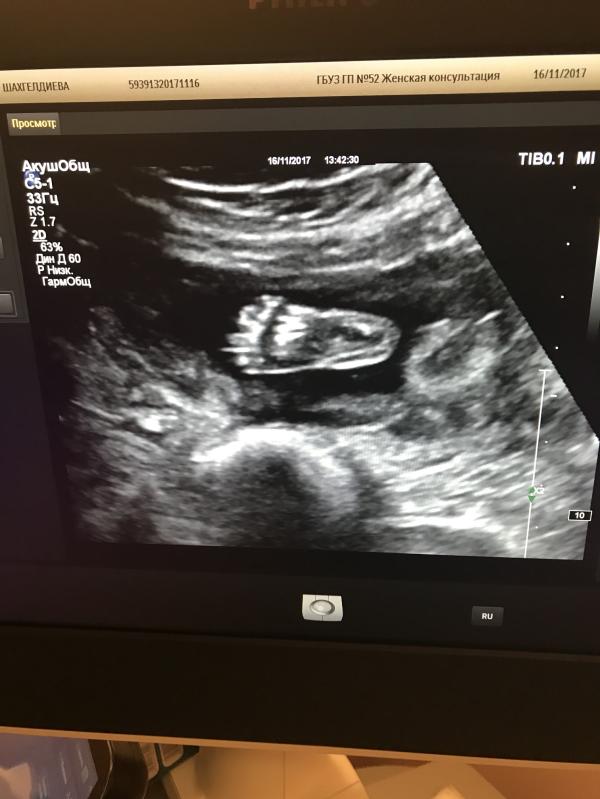

Сходили я на скрининг .

Вроде должно быть хорошее настроение , но ...

Меня смутили слова врача : « меня все устраивает , но не очень нравится сердце ... давайте сделаем ещё одно УЗИ через неделю»

- а что не так с сердцем ?

- не могу ничего пока сказать , посмотрим ещё раз через недельку

Блин , ну как , как мне не нервничать ? Что вообще может быть 😞😭? У меня уже в голове -10000 мыслей